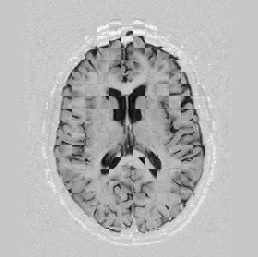

A long optimisation where I changed both the number of knot-points and the resolution is shown in Figures [*] and [*].

Figure: Multi-scale NRR with knot-points increase. From left to right, top then bottom:before NRR; after NRR, level 2, 4 knot-points; after NRR, level 1, 5 knot-points; after NRR, level 0, 10 knot-points. All stages comprised 10 iterations each. The images above apply to the same experiment as in Figure [*], but shown here is a different pair of images.